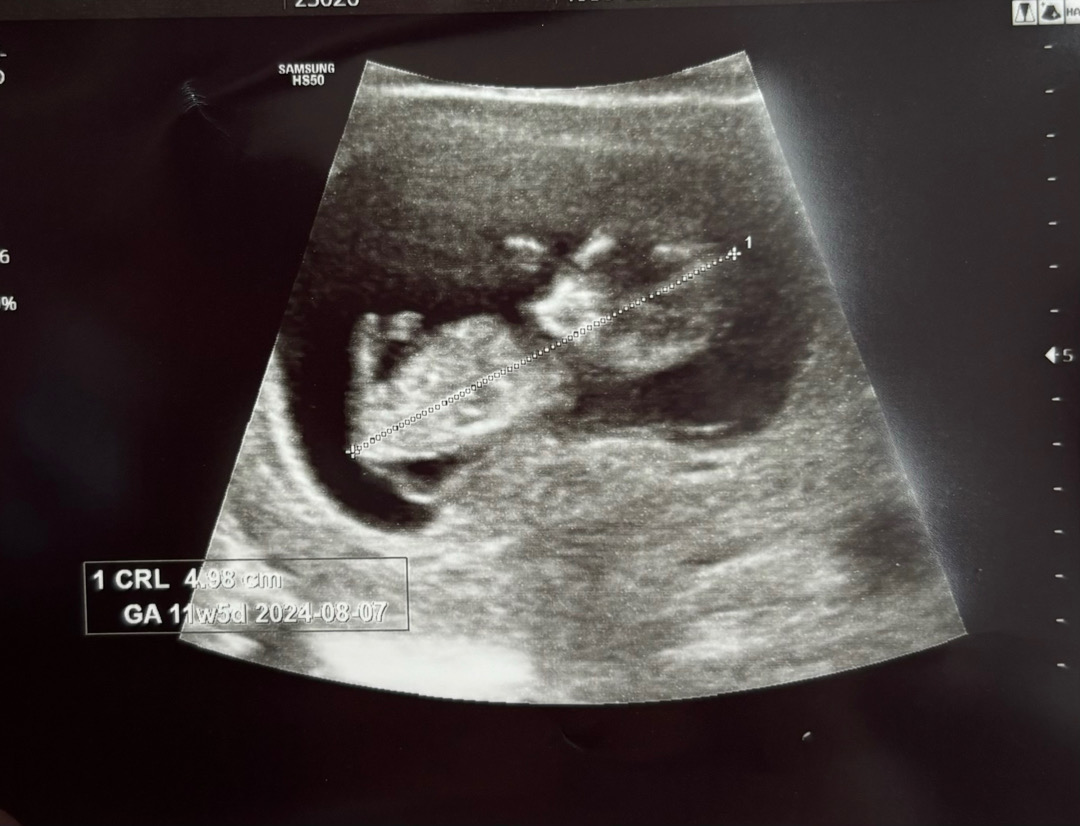

처음에 초음파 보고 출산예정일이 8월 9일이라고 했는데 오늘 기형아 검사 하러가니 아기가 많이 자라서 초음파 상 11주 5일, 8월 7일 출산 예정일이라고 뜨더라구요!! 원래는 오늘이 11주 3일인데 11주 5일로 보는게 맞는건지.. 헷갈리네요 ㅠㅠ